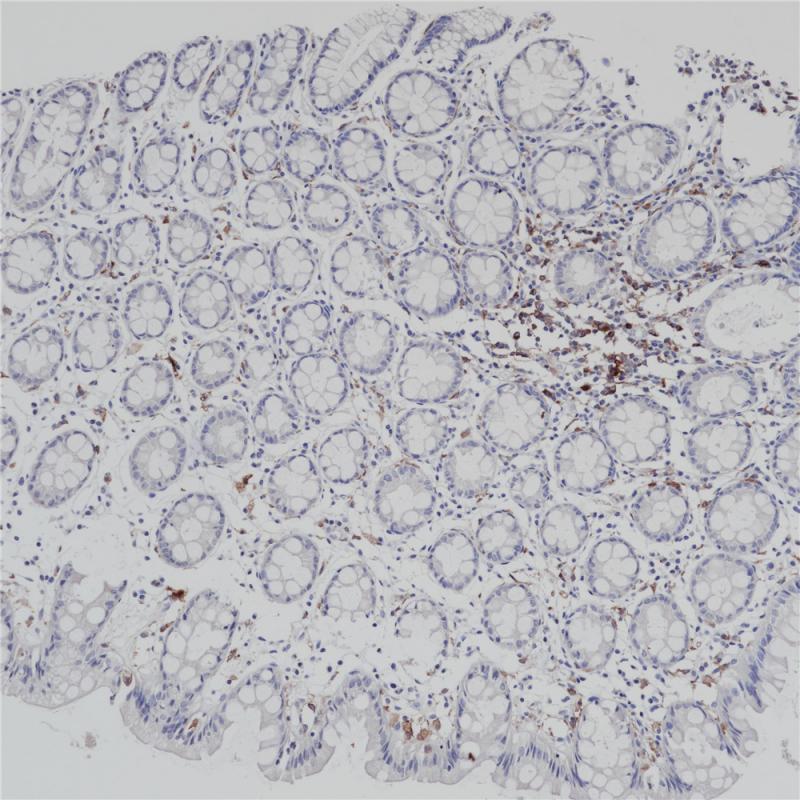

MHC II(DRα chain) 重组兔单克隆抗体

主要组织相容性复合体 II 类(MHC II 类)分子是在巨噬细胞、树突细胞和 B 细胞等抗原呈递细胞表面表达的异二聚体的跨膜糖蛋白。在人体中,MHC II 类蛋白复合体被人白细胞抗原基因复合体 (HLA) 编码。MHC II可在 B 淋巴细胞、活化的 T 淋巴细胞、活化的自然杀伤 (NK) 细胞等表达。

阳性对照

食管